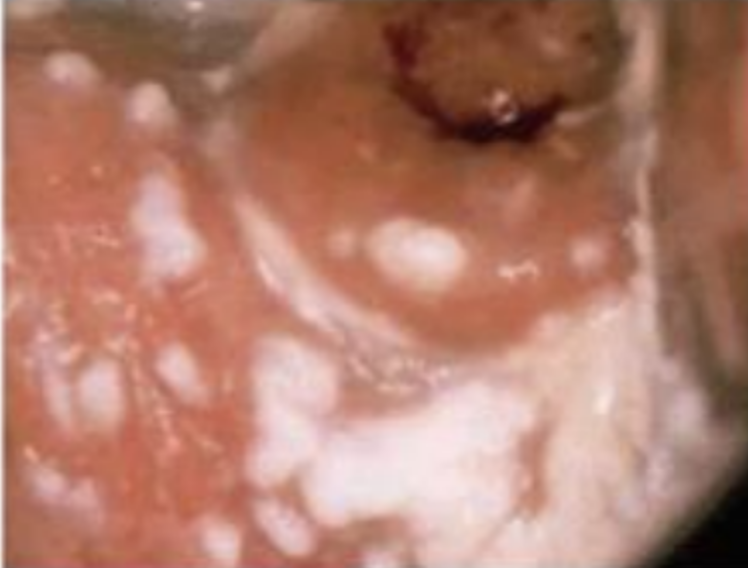

Candidíase

How well did you know this?